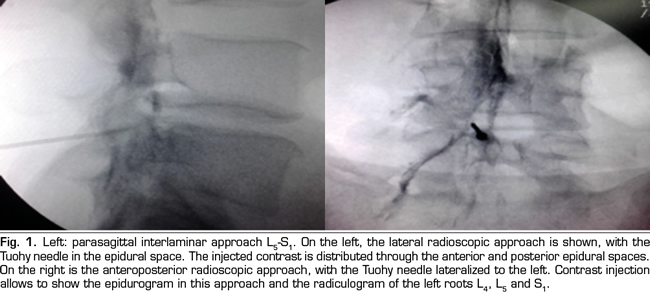

Results: Fifty four patients were treated with epidural betamethasone. In 29 the parasagittal interlaminar route was utilized while 25 were treated by the transforaminal route. A 20 % reduction in baseline VNS was observed with the interlaminar route and 36 % reduction with transforaminal approach. Intensity and Interference Scores were also reduced. This reductions were statistically significant when comparing to baseline data (paired t test) but differences between groups were not significant (unpaired t test). However the number of positive responses as defined above was greater in the transforaminal group, 64 % versus 38 % in the interlaminar group, statistically signifi cant difference using the Chi Square analysis (p=0.01). In patients with positive responses, interlaminar and transforaminal betamethasone produce clinical and statistically significant reductions in pain intensity and interference, without difference between groups.

Conclusion: Epidural betamethasone produced a reduction in pain intensity and interference utilizing the BPI, by the two routes utilized to access the epidural space. Although no statistically differences were observed in this reductions between groups, the frequency of positive responses were higher when the drug is administered by the transforaminal route. Epidural interlaminar parasagittal betamethasone injection is a reasonable alternative to the transforaminal route, without the neurologic complications described utilizing this technique.